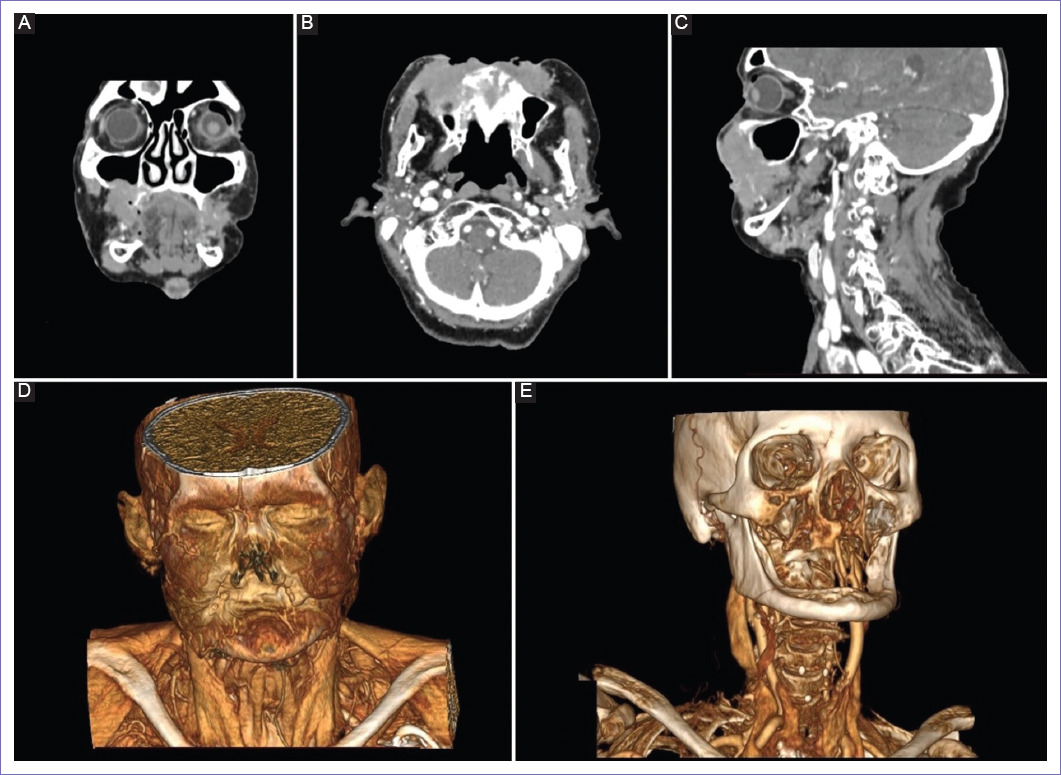

Paciente mujer de 75 años, agricultora, quechua hablante, con lugar de origen en la sierra peruana, que ha estado viviendo sola durante sus últimos 30 años. Refiriendo desde hace 15 años cambio de coloración a nivel de la piel del labio superior, se agrega limitación progresiva de la apertura bucal desde hace cinco años. Llevada forzadamente por nieta al establecimiento de salud, por presentar dolor al abrir la boca. Al examen físico, se observa coloración oscura asociada a costras a nivel de piel de pómulos y comisura de labio superior a predominio derecho. Solo podía abrir un centímetro la cavidad bucal, observándose que es edéntula. La biopsia de labio resultó compatible con adenocarcinoma metastásico, con inmunohistoquímica, CK20 positivo, reportándose negativo para CK7 y sinaptofisina. Se realiza tomografía contrastada de cabeza, cuello, tórax y abdomen completo, revelando una lesión extensa dependiente de labio superior con continuidad al labio inferior de manera bilateral y compromiso óseo de maxilares (Fig. 1). Así mismo, se evidenció una lesión proliferativa de recto medio e inferior. Se completa estudio con colonoscopia y biopsia de lesión de recto, siendo compatible con adenocarcinoma mucinoso. La resonancia magnética de pelvis demostró engrosamiento mural difuso en recto medio e inferior, de aspecto nodular en pared anterior, con 8 cm de longitud, asociado a adenopatías en el mesorrecto, en vasos sacros e iliacos. Catalogándose como cáncer de recto medio e inferior EC IVA por metástasis cutánea facial. Se plantea la opción de radioterapia paliativa a lesión facial y terapia sistémica. Sin embargo, la paciente rechaza el tratamiento. La enfermedad progresa a nivel pulmonar y hepático a las tres semanas, falleciendo a los ocho meses posterior al diagnóstico de metástasis cutánea.

Figura 1 Tomografía computarizada de cabeza y cuello. A: lesión que involucra labio superior e inferior, con predominio superior. B: lesión se extiende a mucosa bucal de carrillos con una extensión de 9 cm. C: destrucción de seno maxilar derecho, con una longitud de 6 cm. D: en la reconstrucción tridimensional se observa lesión infiltrando el músculo orbicular de los labios y el buccinador. E: en la reconstrucción tridimensional se aprecia la destrucción del seno maxilar derecho.